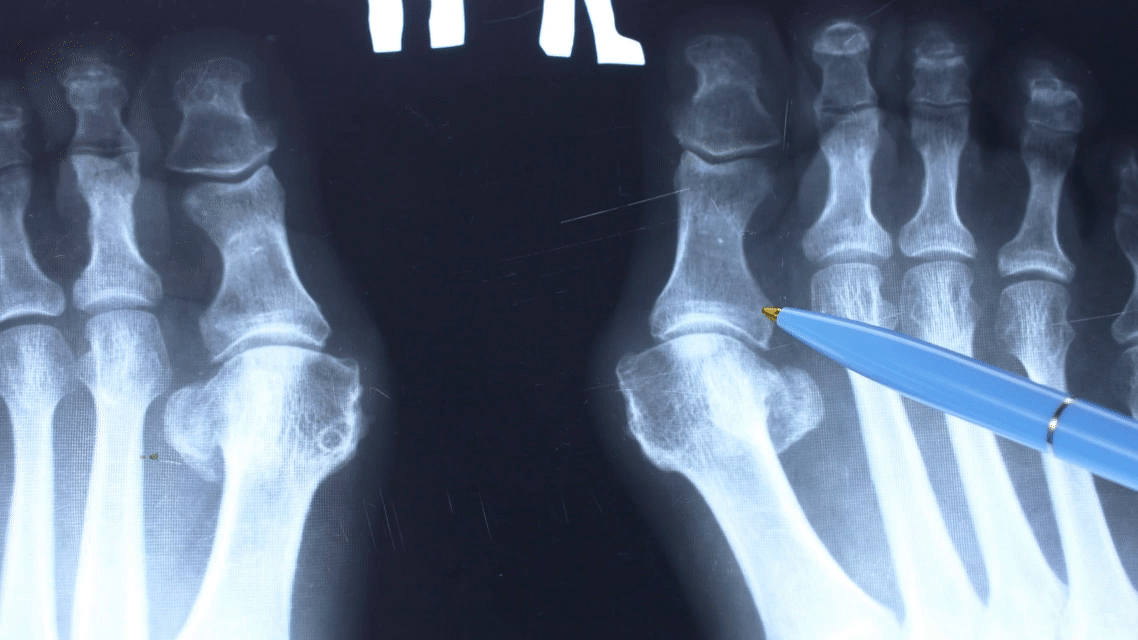

A bunion is a bony bump that forms at the base of the big toe, caused by gradual misalignment of the joint where the toe meets the foot.

This is known as the first metatarsophalangeal joint.

The outward bump is just the tip of the iceberg. What’s really going on is a structural problem deep in the foot.